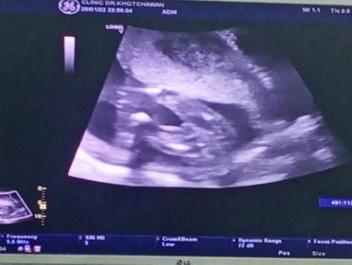

ถามคุณแม่หน่อยนะคะ น้องเป็นชายหรือหญิงพอดีหมอยังไม่บอกเลยคะ..18w

ผู้หญิงรึป่าว 😊

น่าจะหญิงนะคะ